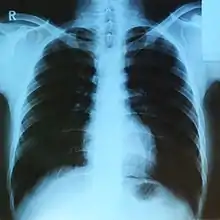

- التصوير الشعاعي في الطب للكشف عن الأسنان والعظام وكسورها وتحديد مواقع الأجسام الصلبة مثل الشظايا أو الرصاص في الجسم، وكذلك الكشف عن الأورام في الجسم، بفضل هذه الأشعة أصبح من الممكن رؤية الكسور العظمية بدقة عالية حيث تستطيع هذه الأشعة اختراق الأجسام اللينة مثل الجلد ولكنها لا تستطيع المرور عبر العظام، مما يؤدي لظهور صورة الأخيرة. من أهم ما يميزها هو قلة أضرارها الجانبية .

- أيضاً يستخدم الأطباء هذه الأشعة في علاج الأورام السرطانية والقضاء عليها. فالأشعة السينية تميت الخلايا السرطانية وتقضي عليها، أما خلايا الجسم السليمة فهي تستعيد حيويتها بعد فترة قليلة وتعود سليمة معافاة.